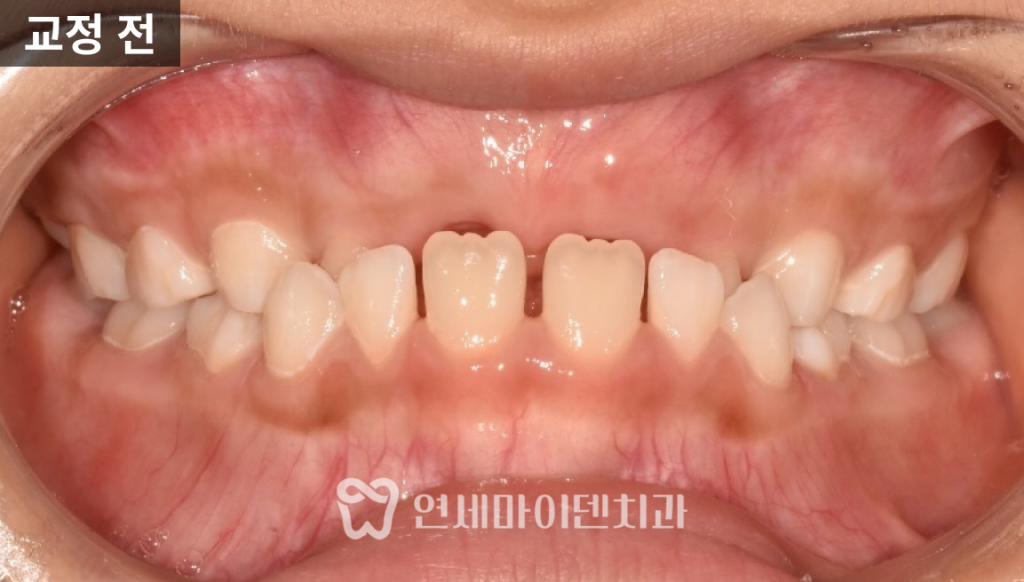

“부정교합이 심하고 영구치가 흔들려요”

이 환자분은 8살 어린이 환자분으로

앞니가 위아래 반대로 물리고 아래 영구치가 흔들려서 오셨습니다.

입안을 살펴보니 아래 앞니 두 개는 영구치였고,

나머지는 유치 상태로 아직 영구치가 맹출 전이었습니다.

특히, 아래 앞니가 위로 솟아올라서

윗니와 거꾸로 물리는 ‘반대교합’이 심한 상태였습니다.

이 상태 그대로 영구치가 모두 자란다면

부정교합과 반대교합이 더욱 심해질 수 있습니다.

따라서 어린 나이지만, 빠른 교정 치료가 필요한 상태였습니다.